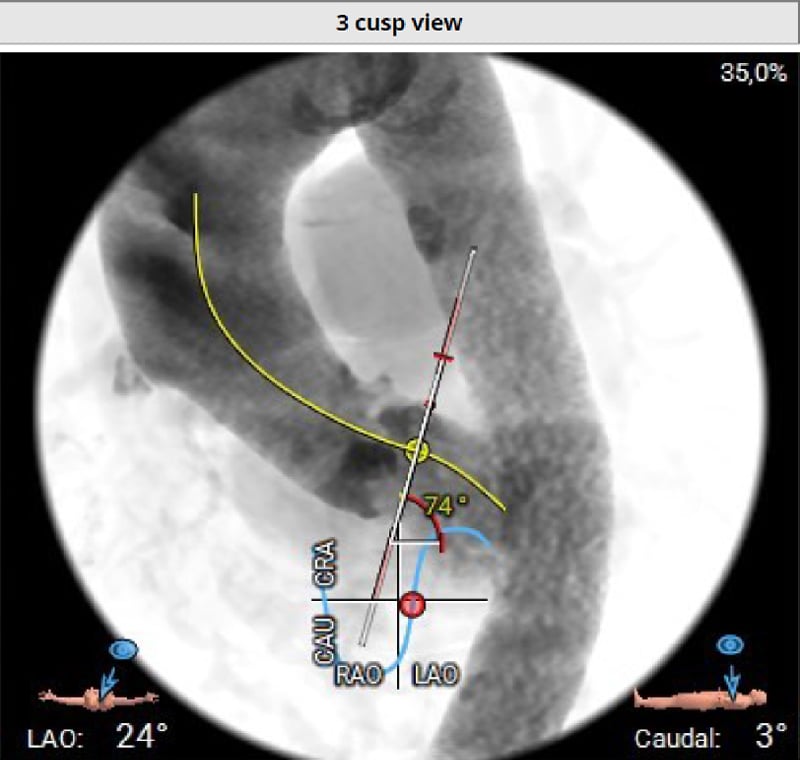

Die Planungs-Computertomographie (Abbildung 2-6) zeigte eine stark verkalkte Aortenklappe (Agatston-Score 3.398, Kalziumvolumen 2.627) mit leicht asymmetrischen Taschenklappen, wobei die nichtkoronare Tasche die größte war. Der linksventrikuläre Ausflusstrakt (LVOT) war verkalkt, beginnend auf Annulusebene bis 5,1 mm in den LVOT unterhalb der linkscoronaren Tasche reichend. Die Aortenwurzeldiameter waren niedrig: Anulus (aus dem Perimeter abgeleiteter Durchmesser 22,3 mm), linker ventrikulärer Ausflusstrakt (LVOT) bei 4 mm (19,9 mm), Sinus valsalva (SOV) (links 24,4 mm, rechts 25,3 mm, noncoronar 27,3 mm) und sinutubulärer Übergang (STJ) (24,0 mm). Darüber hinaus zeigte sich ein geringer Abstand des Ostiums der linken Koronararterie zum Annulus (8,6 mm) und eine horizontale Aorta (74°). Die Aorta, die Iliaca und die Femoralarterien waren für einen transfemoralen Zugang geeignet.

Abbildung 6: Computertomographie - horizontale Aorta

- Horizontale Aorta mit 74°

Anschließend wurde das korrekte Crimpen der Navitor Vision 25 mm unter Durchleuchtung überprüft. In einer C-Bogen-Angulation mit Exposition des LCA Ostiums (LCA-view: LAO 31 CRA 10) erfolgte eine Prädilatation der nativen Aortenklappe mit einem 20 mm semi-compliant Ballon (VACS III) unter ventrikulärer Schrittmacherstimulation (180-200/min). Während der vollständigen Balloninflation erfolgte eine Aortographie, die eine ausreichende Distanz zwischen der linken Taschenklappe und dem LCA Ostium zeigte. Die Länge der linkskoronaren Tasche erscheint kürzer als der Abstand des Anulus zur Koronararterie (Abbildung 8, Video 1).

Nach Entfernung der 14F-Schleuse wird die Navitor-Prothese schleusenlos und der Einführungskatheter über die AFC re eingeführt, der flush-port wird auf 12 Uhr orientiert. Die Passage des Aortenbogens und der Aortenklappe waren unkompliziert. Beginnend in der Cusp-Overlap-Projektion(LAO 13 CAU 36) wurde die Klappe langsam und kontrolliert unter wiederholten Injektionen geringer Kontrastmittelmengen über den non-koronar platzierten Pigtail-Katheter implantiert (Video 2).

Obwohl eine extrem horizontale Aorta vorlag, war die Implantation der selbstexpandierenden intra-annulären Klappe unkompliziert, ohne dass es eine Repositionierung / Re-Sheating erforderlich war. Eine bewusst langsame Prothesenfreisetzung hilft, die Klappe positionsstabil bis zur vollständigen Expansion zu implantieren

Die kontrastmittelverstärkte Computertomographie zeigte spezifische anatomische Herausforderungen: a) trikuspide Aortenklappe mit massiver Verkalkung (Agaston-Score 3,398), b) Verkalkungen des linkskoronren Annulus bis in den linksventrikulären Ausflusstrakt (LVOT) reichend, c) kleiner Aortenklappenannulus mit einem Durchmesser von 22 mm und schmalem 19 mm LVOT, d) kleine Aortenwurzeldimensionen, d) 8.6 mm Abstand des LCA-Ostiums zur Annulusebene und e) eine 74° horizontale Aorta.

Die Fallpräsentation unterstreicht die Bedeutung einer dezidierten CT-Analyse zur Identifizierung spezifischer anatomischer Besonderheiten und zur Bestimmung der C-Bogen-Angulationen für eine optimale Visualisierung der prozedurrelevanten Strukturen. Neben der, insbesondere für die Implantation von selbstexpandierenden Transkatheterklappen etablierten cusp-overlap-Projektion, wurde in diesem Fall eine LCA-Projektion verwendet, um die räumliche Nähe zwischen nativem linkskoronaren Aortenklappensegel und dem LCA Ostium während der Valvuloplastie, die unter simultaner Aortenwurzelangiographie durchgeführt wurde, zu beurteilen.